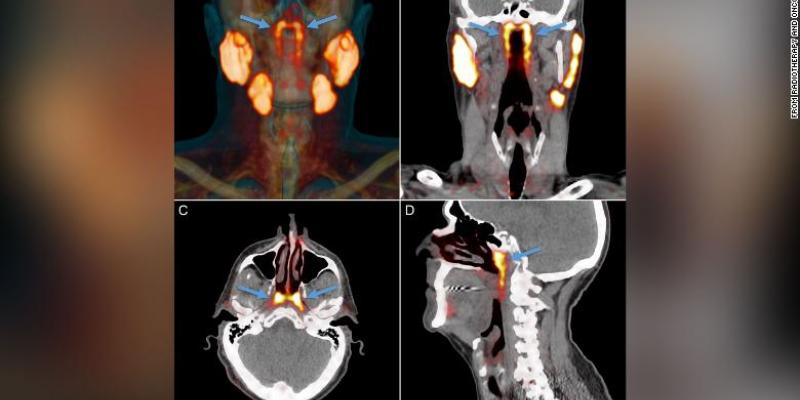

Según ha publicado la CNN, los investigadores encontraron por primera vez la parte del cuerpo, que proponen nombrar glándulas tubarias, durante una exploración diseñada para buscar crecimientos tumorales, ha señalado el autor principal del estudio, Matthijs H. Valstar, cirujano del departamento de oncología y cirugía de cabeza y cuello del Instituto del Cáncer de Países Bajos.

Asimismo, los científicos observaron escaneos de la cabeza y el cuello de otras 100 personas que estaban tratando por cáncer de próstata y diseccionaron dos cadáveres, uno masculino y otro femenino. En todos los análisis encontraron las glándulas, según se publicó en la revista Radiotherapy and Oncology.

Las glándulas no se pueden ver con métodos convencionales de imágenes médicas como ultrasonido, tomografías computarizadas o imágenes de resonancia magnética. El nuevo órgano solo se identificó cuando los médicos utilizaban un tipo de exploración nuevo y avanzado llamado PSMA PET/CT que se ha utilizado para detectar la propagación del cáncer de próstata.

PSMA PET es la abreviatura de la obtención de imágenes de antígeno de membrana específico de la próstata mediante tomografía por emisión de positrones. "Las personas tienen tres conjuntos de glándulas salivales grandes, pero no allí". Así dijo el autor del estudio Wouter Vogel, un oncólogo radioterapeuta del Instituto del Cáncer de los Países Bajos.